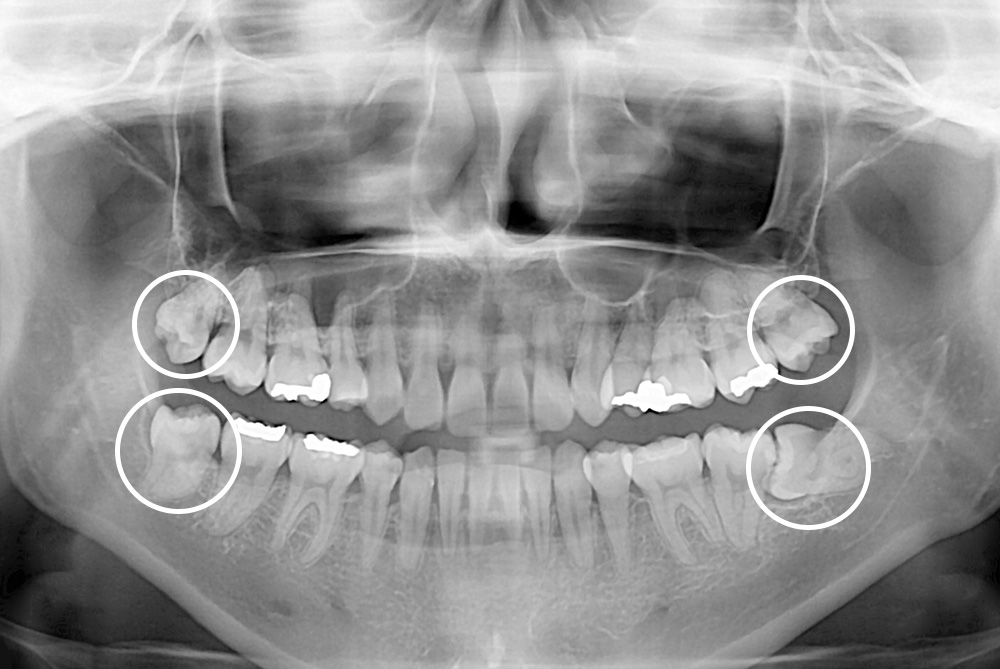

[사랑니] 매복 사랑니 발치

치료전 : 2019-07-18